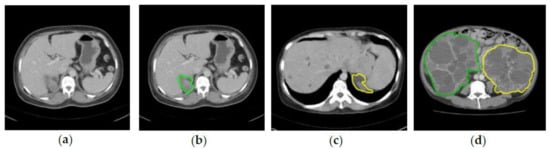

2.2. Ground Truth Annotation

2.3.3. Bounding Box Labeling